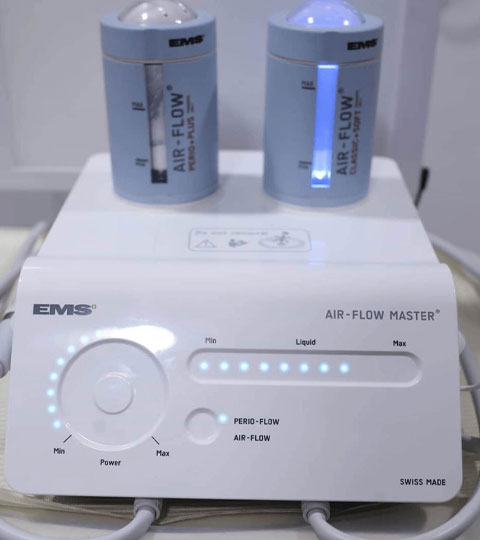

- Dental Facilities